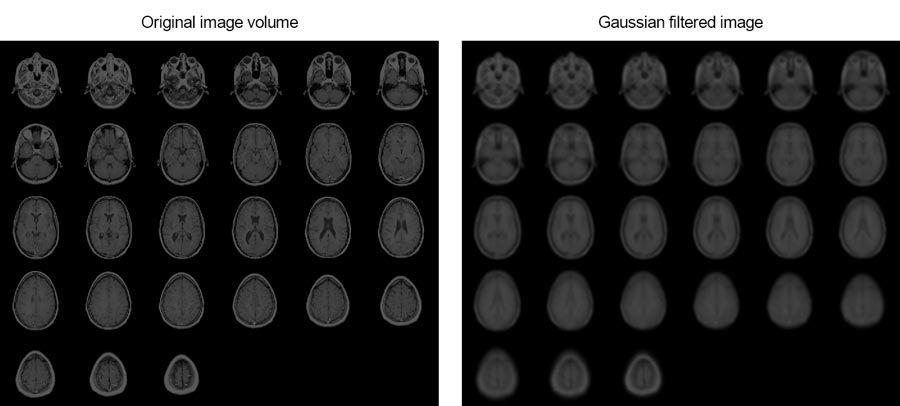

With MATLAB, you can reduce noise or enhance images using a variety of image filtering techniques like Gaussian filtering, box filtering, or image morphology.

This example shows how you can smooth MRI images of a human brain using 3D Gaussian filtering.